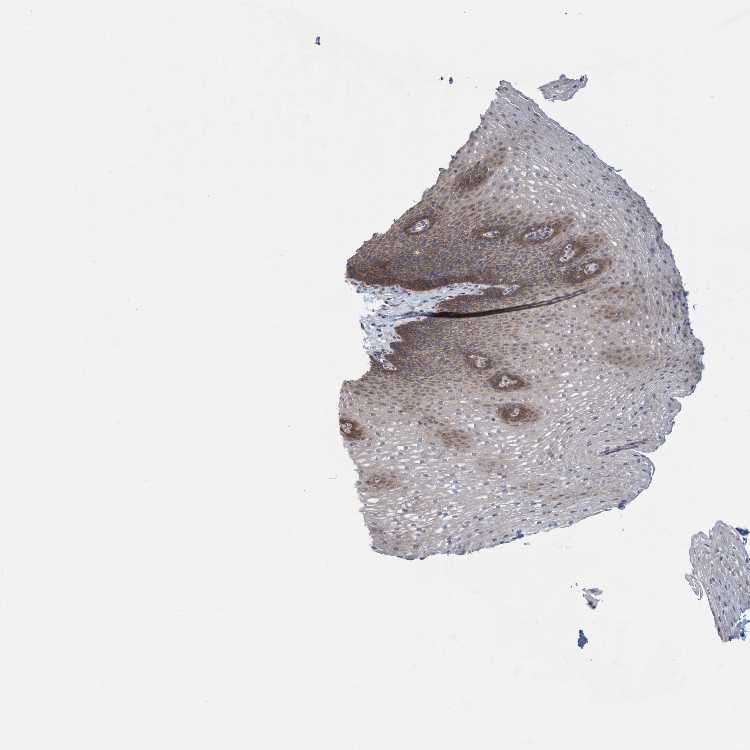

ESOPHAGUS - Antibody stainingi

Antibody staining in the annotated cell types in the current human tissue is reported as not detected, low, medium, or high, based on conventional immunohistochemistry profiling in selected tissues. This score is based on the combination of the staining intensity and fraction of stained cells.

Each image is clickable and will lead to virtual microscopy that enables deeper exploration of all samples and also displays staining intensity scores, fraction scores and subcellular localization as well as patient and tissue information for each sample.

Antibody HPA023450

Squamous epithelial cells Medium